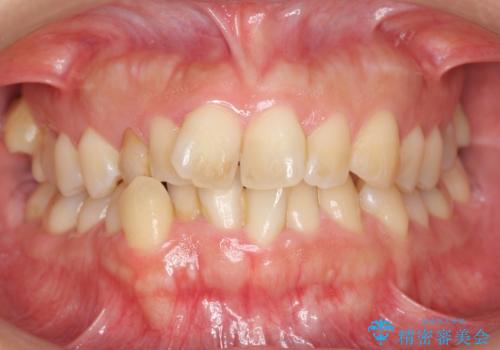

[40代女性] 口元を引っ込めたい 大きく改善

- 口元の突出感を気にして来院。

ガタつきは少ないですが、上下前歯が前方に突出した、上下顎前突でした。

下の前歯を支える骨が薄く、歯肉退縮のリスクがありました。

抜歯して前歯を後方に下げる治療を希望されたため、様子を見ながら移動をしていくことにしました。

上下小臼歯を抜歯しています。

![[40代女性] 口元を引っ込めたい 大きく改善の治療前](https://seimitsushinbi.jp/wp/wp-content/uploads/2018/01/C65-500x350.jpg)